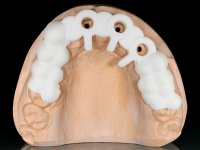

O paciente foi observado conjuntamente e a dúvida que surgiu de imediato foi se seria possível com a regeneração óssea a efectuar poder ser reabilitada naturalmente a zona das papilas interdentárias. Nesse sentido foi feito um enceramento de diagnóstico que contemplaria as duas hipóteses, utilizando ou não a cerâmica gengival. A confecção desse enceramento foi fundamental para expor ao paciente a dificuldade da reabilitação. O wax-up deu origem a um mock-up que foi aprovado pelo paciente e que simultaneamente serviu de guia imagiológica. O caso foi planificado cirurgicamente e realizada uma guia cirúrgica com que foram colocados os implantes. Após 10 semanas foi feita a 1ª impressão para confecção da ponte provisória. Foram criados os primeiros perfis de emergência na gengiva artificial e foi digitalizado o modelo. Por processo de CAD-CAM foi confeccionada uma ponte provisória aparafusada baseada no enceramento de diagnóstico. A ponte trabalhou durante 8 semanas os tecidos moles que foram fielmente copiados numa impressão com técnica de moldeira aberta. Os transferes foram individualizados com resina composta para copiarem fielmente os perfis de emergência criados pela ponte provisória. Confeccionado o modelo de trabalho definitivo, foi realizada uma infra-estrutura em zircónio seguindo a orientação do enceramento de diagnóstico. O assentamento da infra-estrutura foi testado em boca e simultaneamente foi novamente impressionados os tecidos moles com um silicone fluido. Nessa consulta foi feito o levantamento da cor. Os dentes 13 e 23 apresentavam uma saturação anormalmente forte que resolvemos não valorizar, optando por privilegiar a relação com o sector antero-inferior. Foi realizada uma nova gengiva artificial com a impressão que acompanhou a impressão de arrasto com a infra-estrutura. Após a colocação da cerâmica na infra-estrutura foram coladas as meso-estruturas. O trabalho final foi aparafusado lentamente permitindo a adaptação dos tecidos moles.